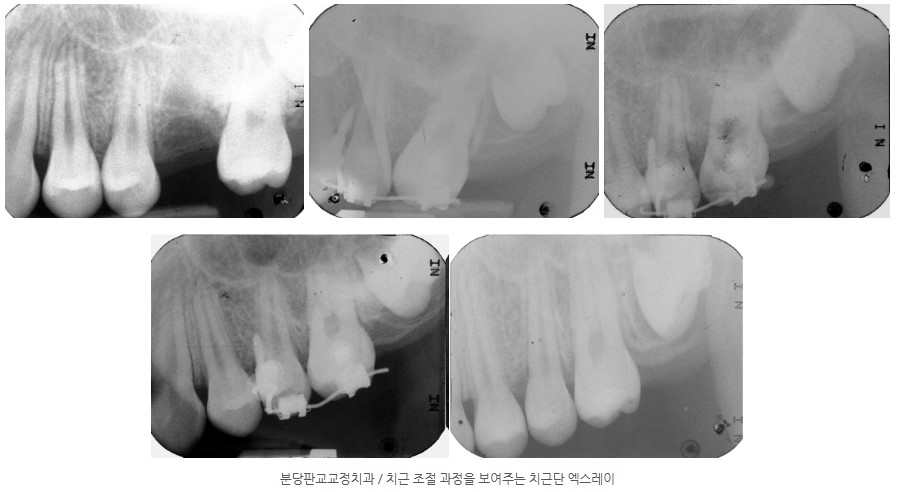

4. 치료 경과 – 공간 폐쇄와 치근 조절

4-1. 공간 폐쇄까지

치료 시작 후 약 10개월 경과 시점에,

치관 사이의 공간은 거의 완전히 폐쇄된 상태가 되었습니다.

그러나 이 시점에서 제2대구치의 치근 방향을 확인했을 때, 치근이 이상적인 방향으로 완전히 직립되어 있지는 않았습니다.

따라서 “공간이 닫혔다”는 이유만으로 장치를 제거하지 않고,

-

치근이 보다 수직에 가깝게

장기적인 교합 안정에 유리하도록

추가적인 치근 조절 단계를 더 진행했습니다.